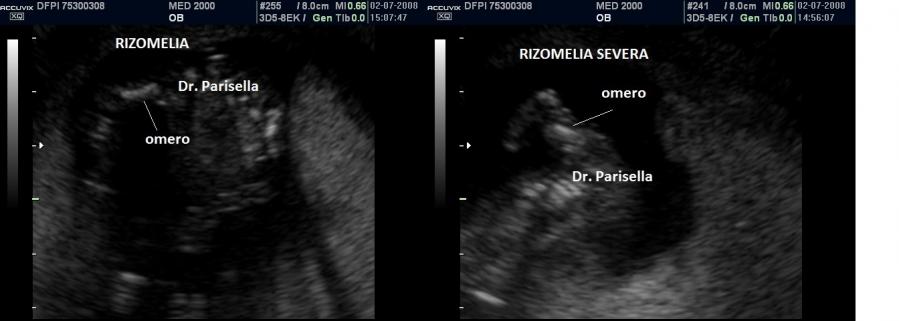

All'ecografia prenatale si riscontra ipoplasia toracica (torace stretto e coste corte), rizomelia lieve-moderata e frequentemente  displasia renale policistica.

Essendo la brevità degli arti frequentemente modesta la diagnosi prenatale è difficoltosa prima del terzo trimestre e comunque non può essere fatta prima della 24a settimana di gestazione.